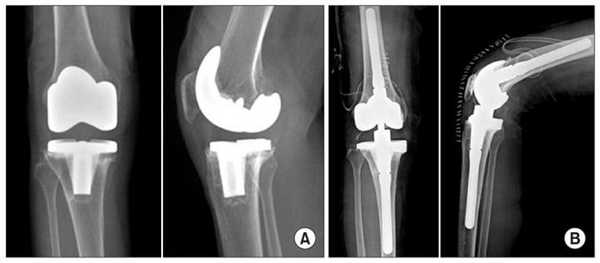

Две техники операции у одного пациента.

Типы протезов и связанные с ними методики

Вы уже знаете, что бывает полное и частичное эндопротезирование коленного сустава, где в первом случае лечение подразумевает полноценную замену суставных поверхностей, а во втором - имплантацию поврежденного участка одного из мыщелков. Соответственно, протезы классифицируются на тотальные, одномыщелковые и ревизионные для замены импланта.

- После постановки однополюсной системы максимально сохраняется собственный костно-хрящевой сегмент и не затрагиваются связки, кстати, они должны быть в хорошем состоянии.

Сравнение двух типов операций.